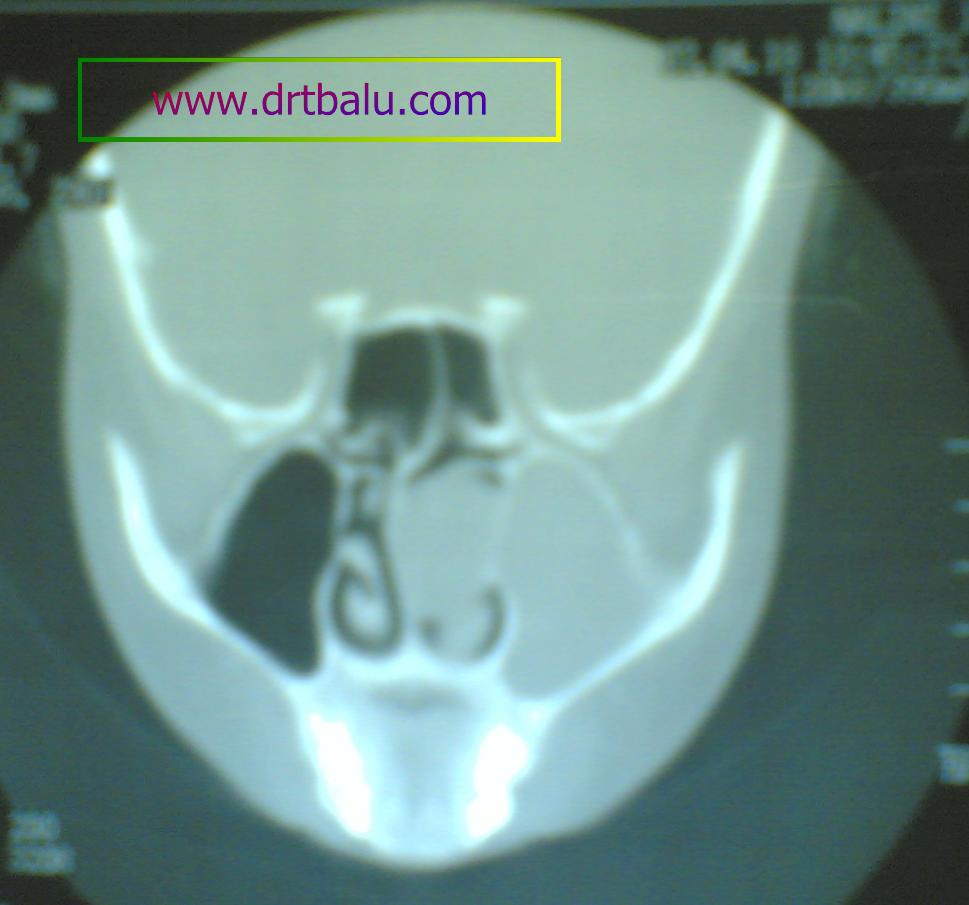

CT scan of paranasal sinuses is diagnostic. It will show the polyp filling the maxillary antrum and exiting out through the accessory ostium into the nasal cavity.

Coronal CT image showing antrochoanal polyp

The antrochoanal polyp is dumb bell shaped with three components i.e. antral, nasal and nasopharyngeal.